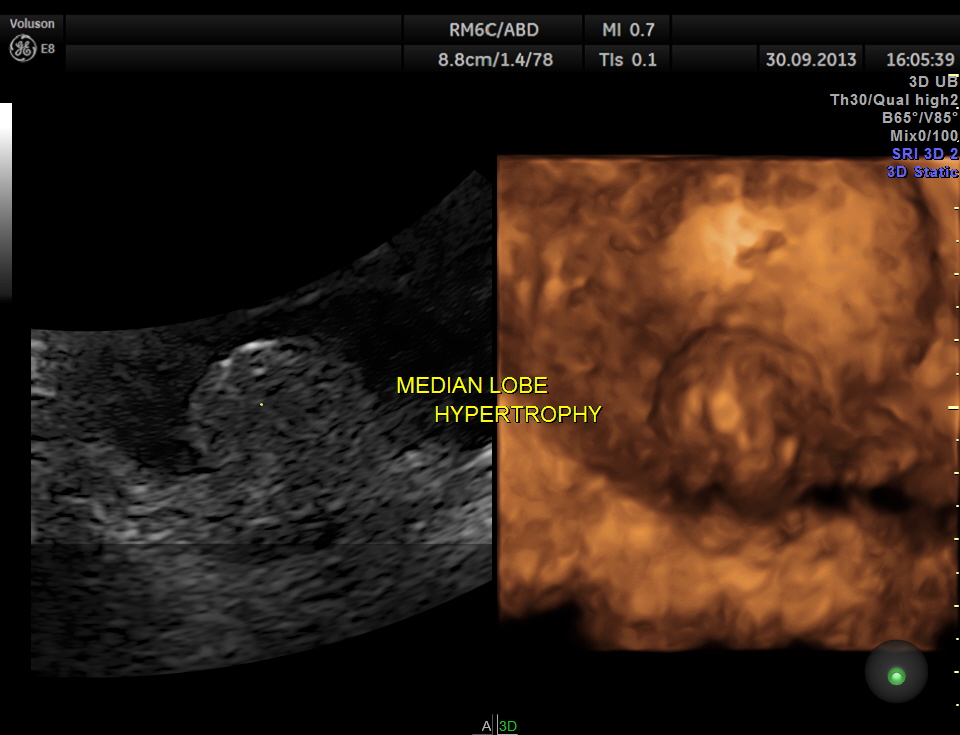

2 D and 3 D views of the median lobe hypertrophy

the median lobe hypertrophy in 2 D